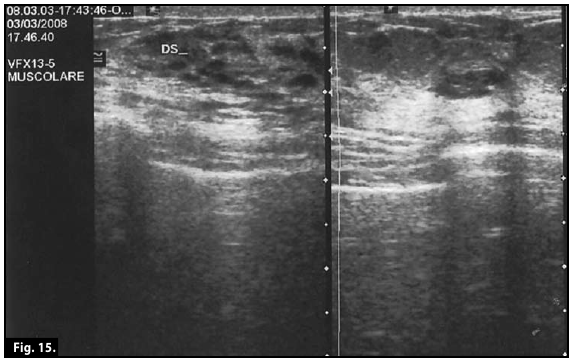

Ultrasound scan...